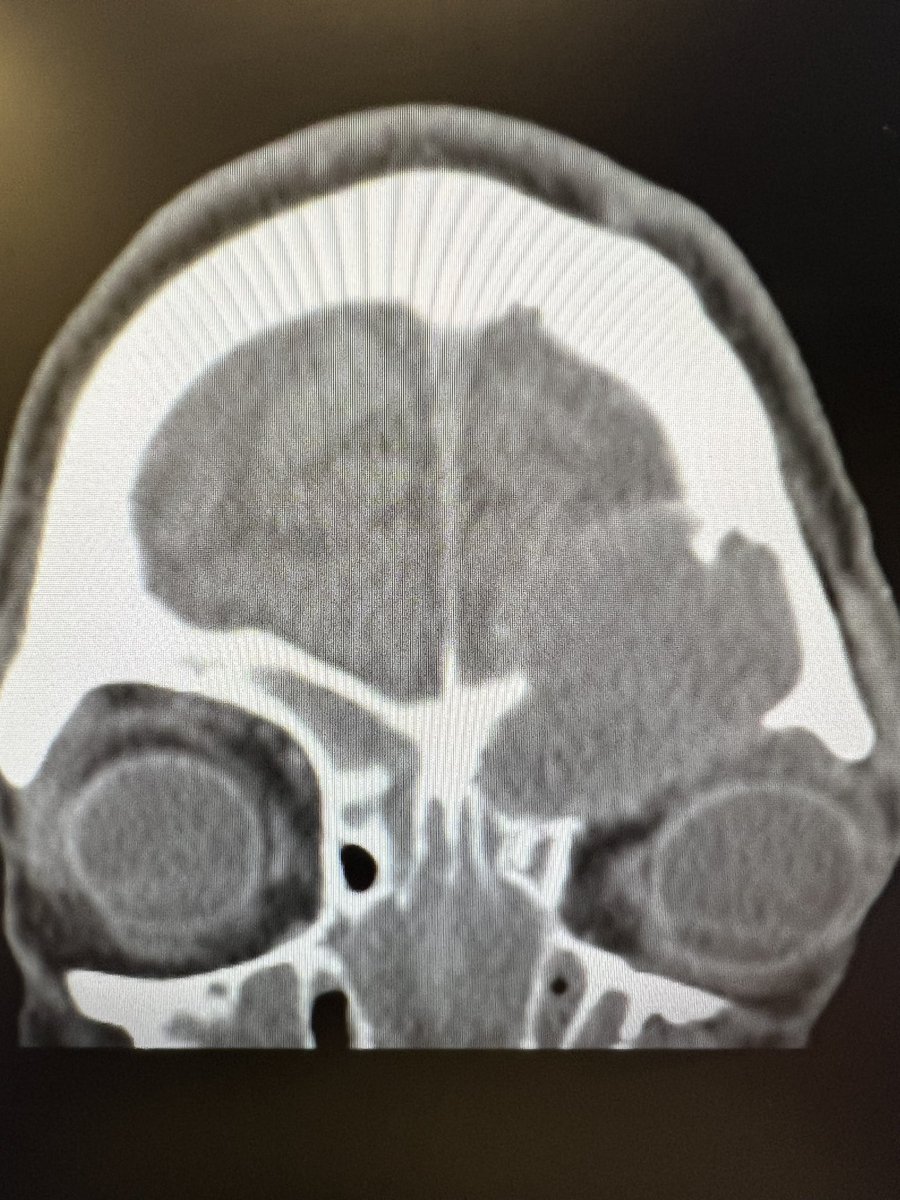

Just sharing the link to my case submission on MACS that is now available on the Cushing’s Hub website as an interactive case study. cushingshub.com/case-studies/a… @springermeded #Endotwitter